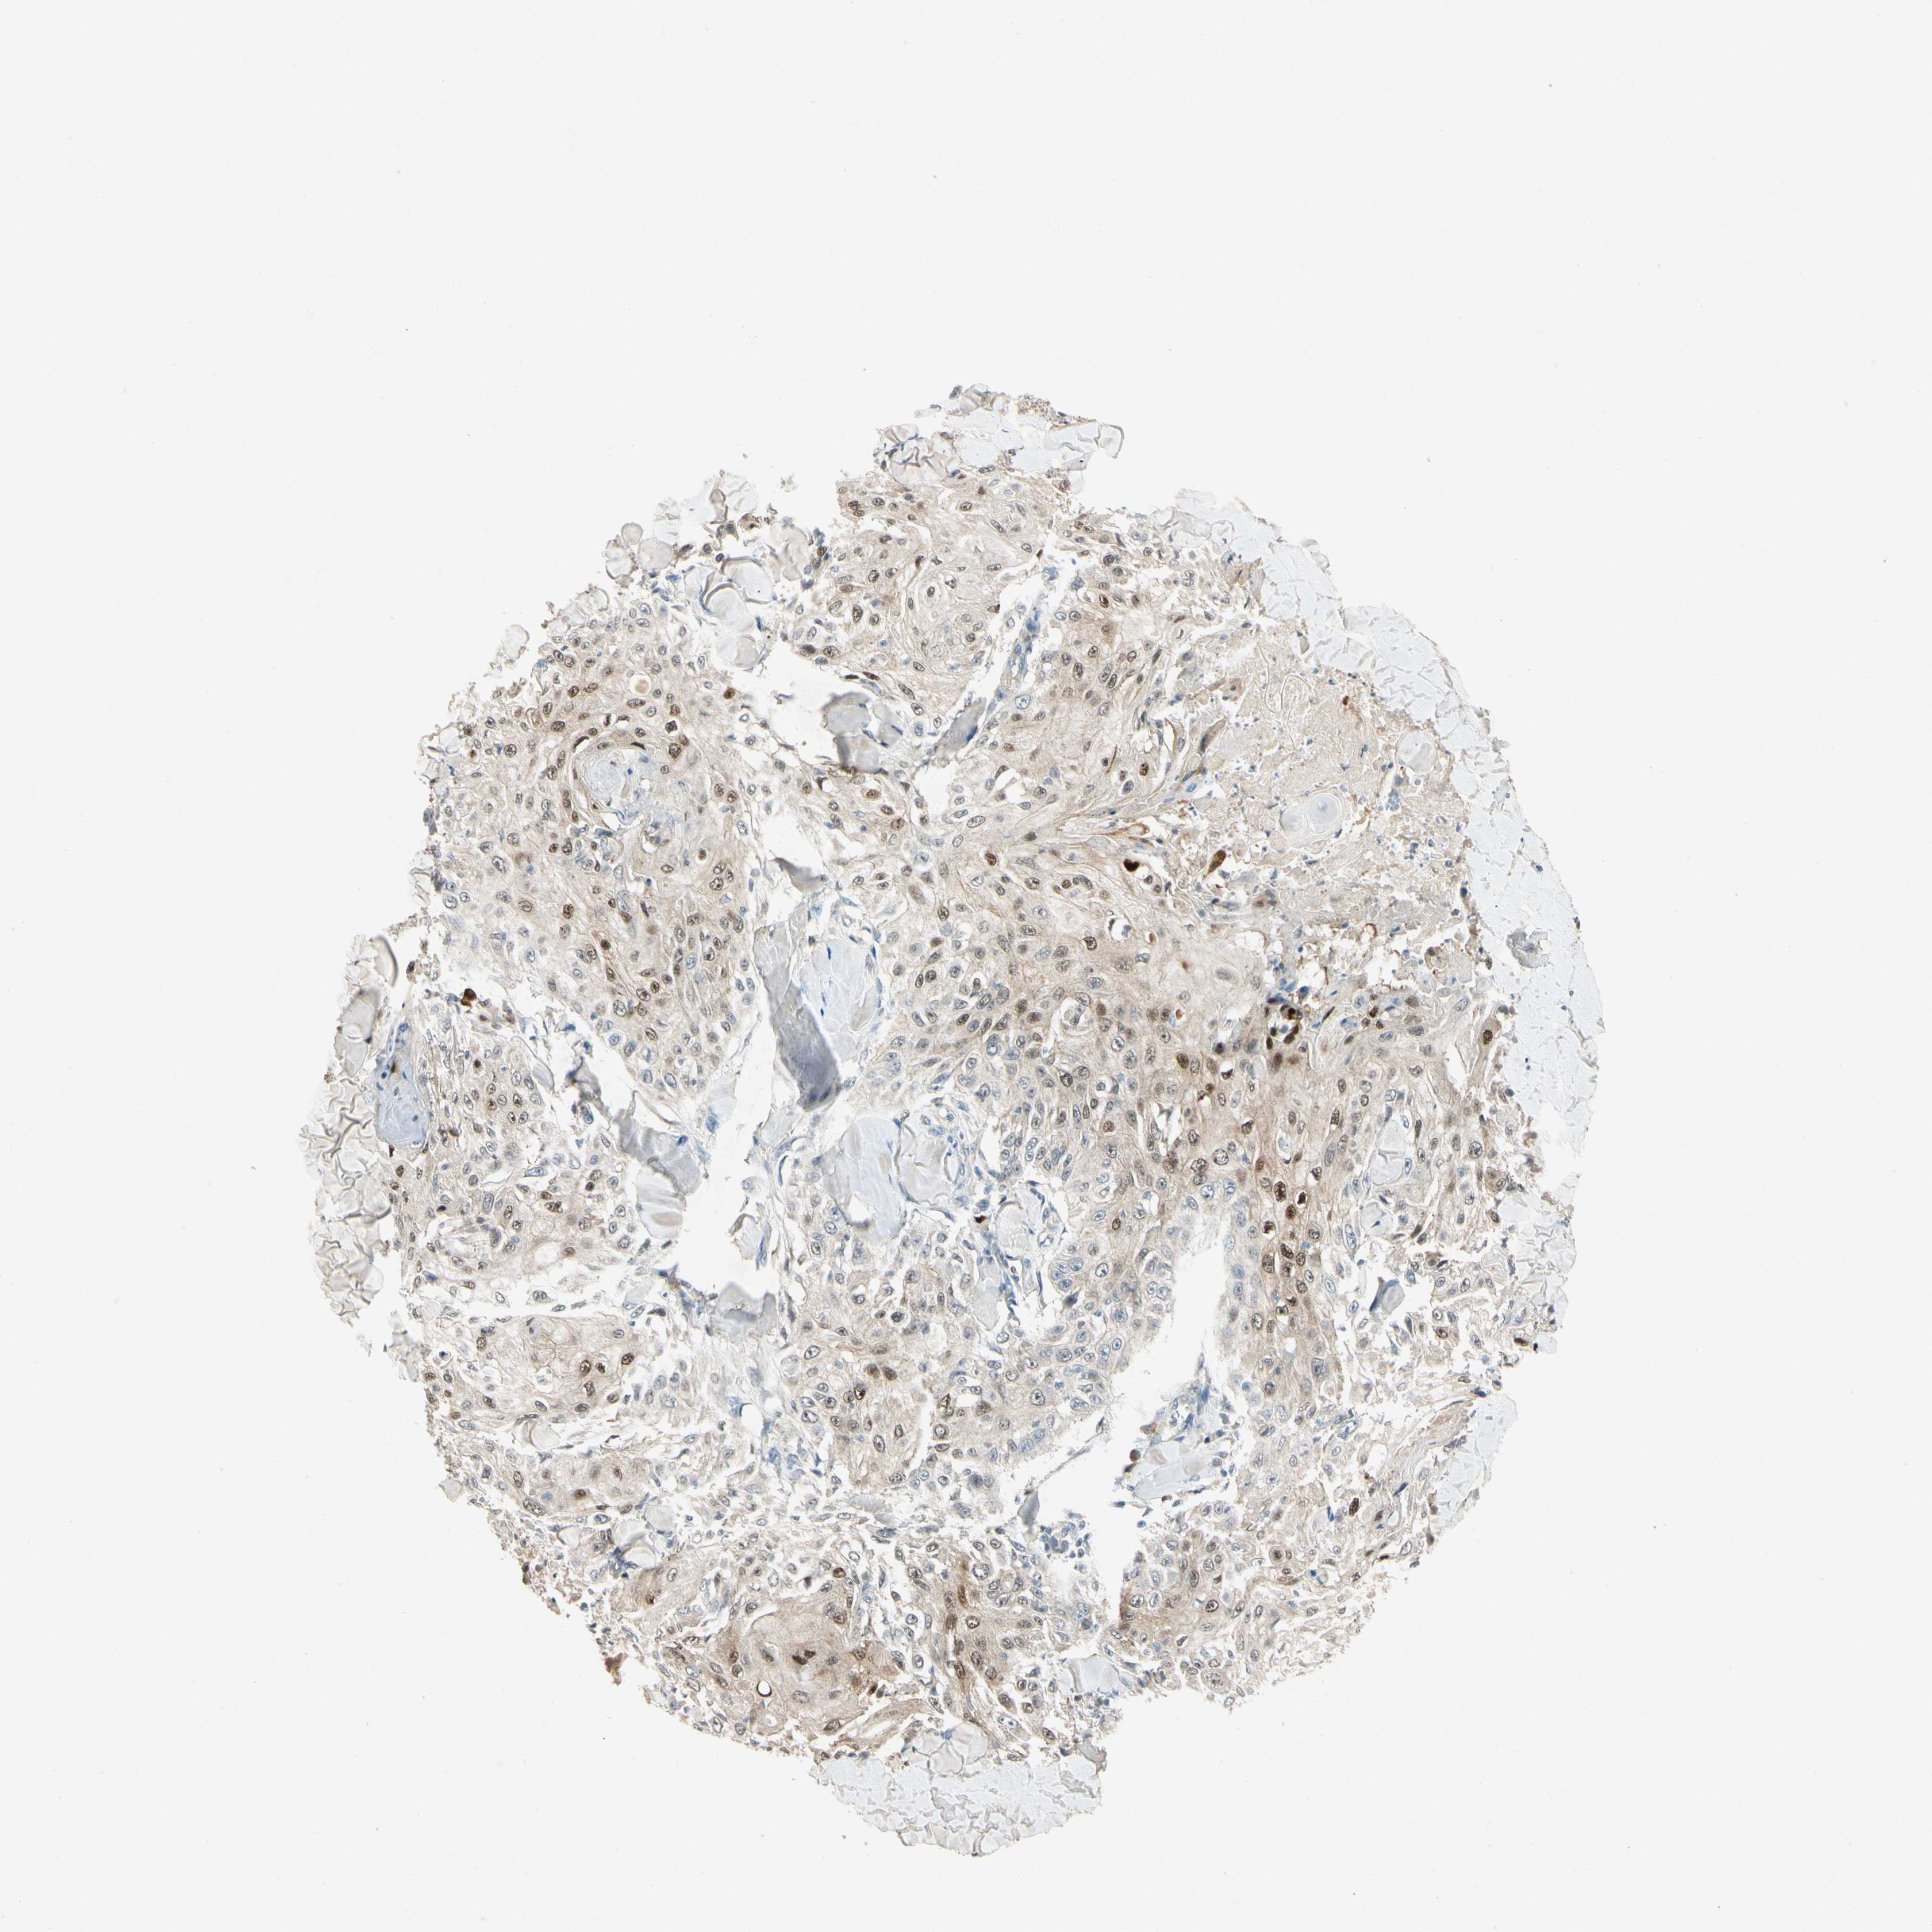

SKIN CANCER - Protein expressioni

A mouse-over function shows sample information and annotation data. Click on an image to view it in a full screen mode. Samples can be filtered based on level of antibody staining by selecting one or several of the following categories: high, medium, low and not detected. The assay and annotation is described here.

Antibody staining in the annotated cell types in the current human tissue is reported as not detected, low, medium, or high, based on conventional immunohistochemistry profiling in selected tissues. This score is based on the combination of the staining intensity and fraction of stained cells.

Each image is clickable and will lead to virtual microscopy that enables deeper exploration of all samples and also displays staining intensity scores, fraction scores and subcellular localization as well as patient and tissue information for each sample.

Antibody HPA052504

Antibody CAB008640

Basal cell carcinoma

Squamous cell carcinoma, NOS

Squamous cell carcinoma, metastatic, NOS

Papilloma, NOS